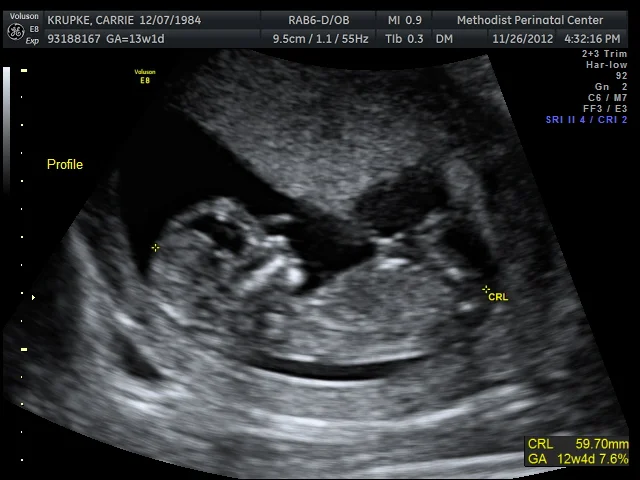

*that we were able to see and hear the heartbeat and get an audio recording. (Gerard thinks I have a train growing inside me. And judging by this photo, our child is already wielding a sword.)